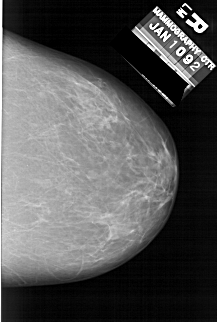

A_1634_1.LEFT_CC

LEFT_CC LINES 6361 PIXELS_PER_LINE 4006 BITS_PER_PIXEL 12 RESOLUTION 43.5 OVERLAY